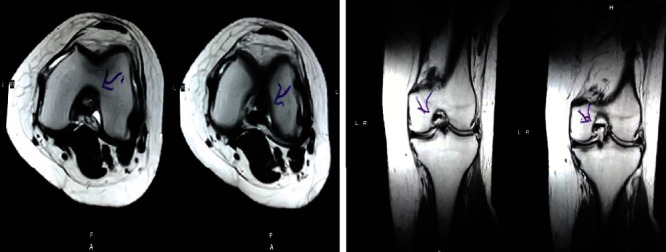

治療后一個(gè)月進(jìn)行隨訪(fǎng)。在第一次細(xì)胞治療后,患者的疼痛明顯減輕。第二次療程后,她沒(méi)有疼痛,并注意到運(yùn)動(dòng)范圍有所改善。持續(xù)的物理治療也觀(guān)察到下肢肌肉力量的增加。從治療開(kāi)始(11個(gè)月前)到最后一次隨訪(fǎng)(4個(gè)月前),患者按照建議的飲食和基于運(yùn)動(dòng)的方案減重了11公斤。因此,她現(xiàn)在整體身體健康,能夠更舒適地進(jìn)行日常生活活動(dòng)。表3顯示治療前后的MRI檢查結(jié)果。人物的圖1和的和圖2顯示半月板撕裂的治療前和治療后(1年后)圖片。觀(guān)察到損傷程度的改善圖2。